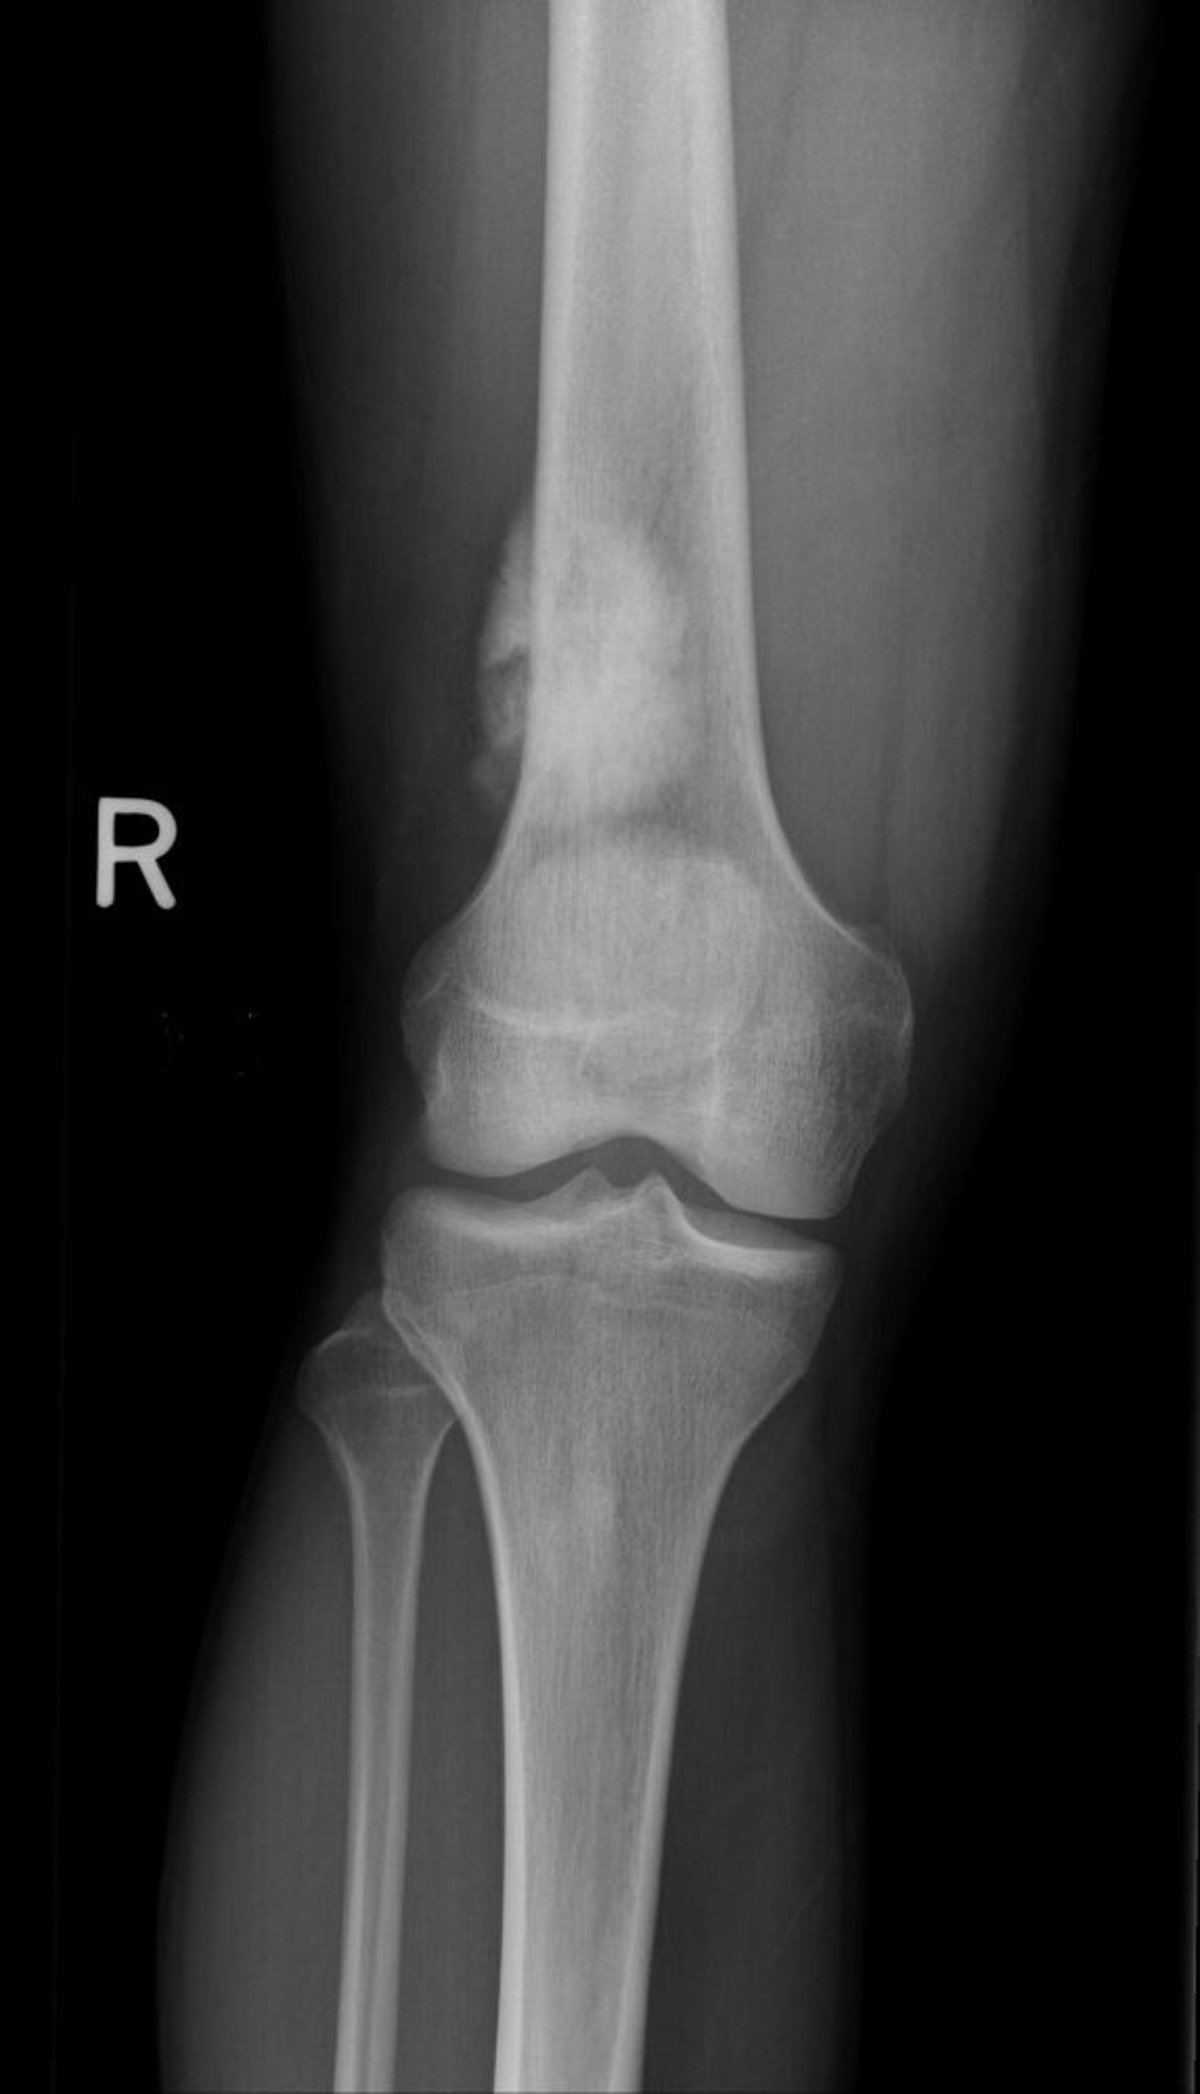

Cette radiographie du genou montre un ostéosarcome au niveau de l’os de la cuisse, au-dessus du genou.

Image publiée avec l’aimable autorisation des Drs Michael J. Joyce et Hakan Ilaslan.